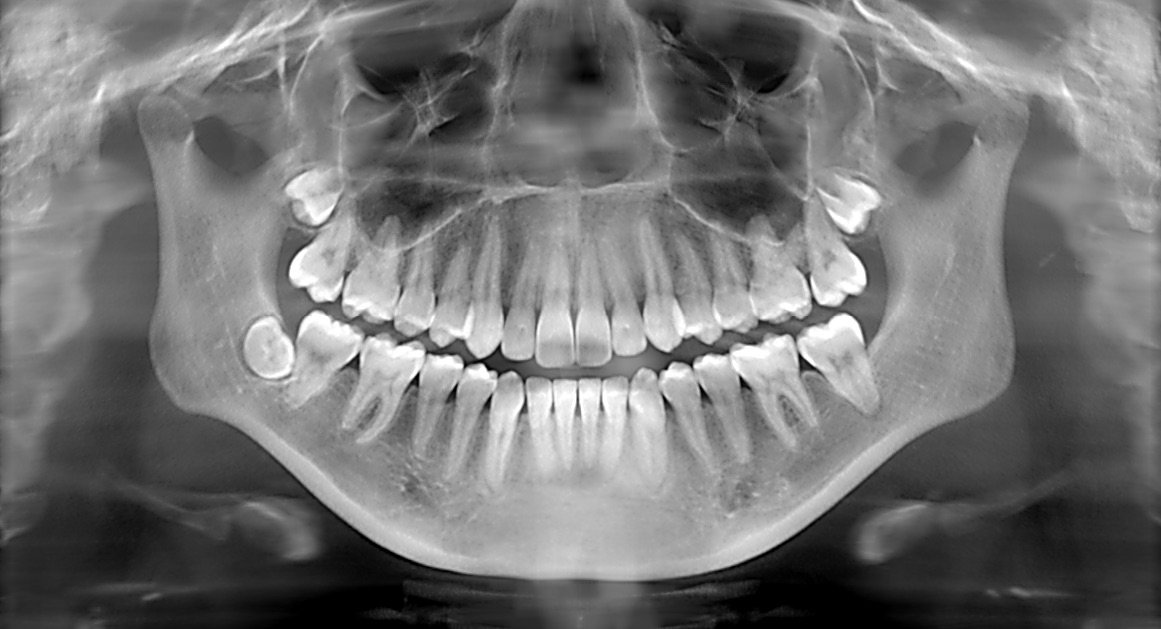

Riya was apprehensive yet hopeful as she underwent the X-ray procedure. It was quick and painless, and within minutes, Dr. Mehta had a comprehensive view of her oral health. The images revealed a hidden cavity and early signs of gum disease—issues that were not visible during her routine check-ups.

Dr. Mehta meticulously explained the results, providing Riya with a clear treatment plan tailored to her unique needs. Armed with this newfound insight, Riya felt a sense of relief and empowerment. She finally understood the root cause of her discomfort and was ready to tackle it head-on.